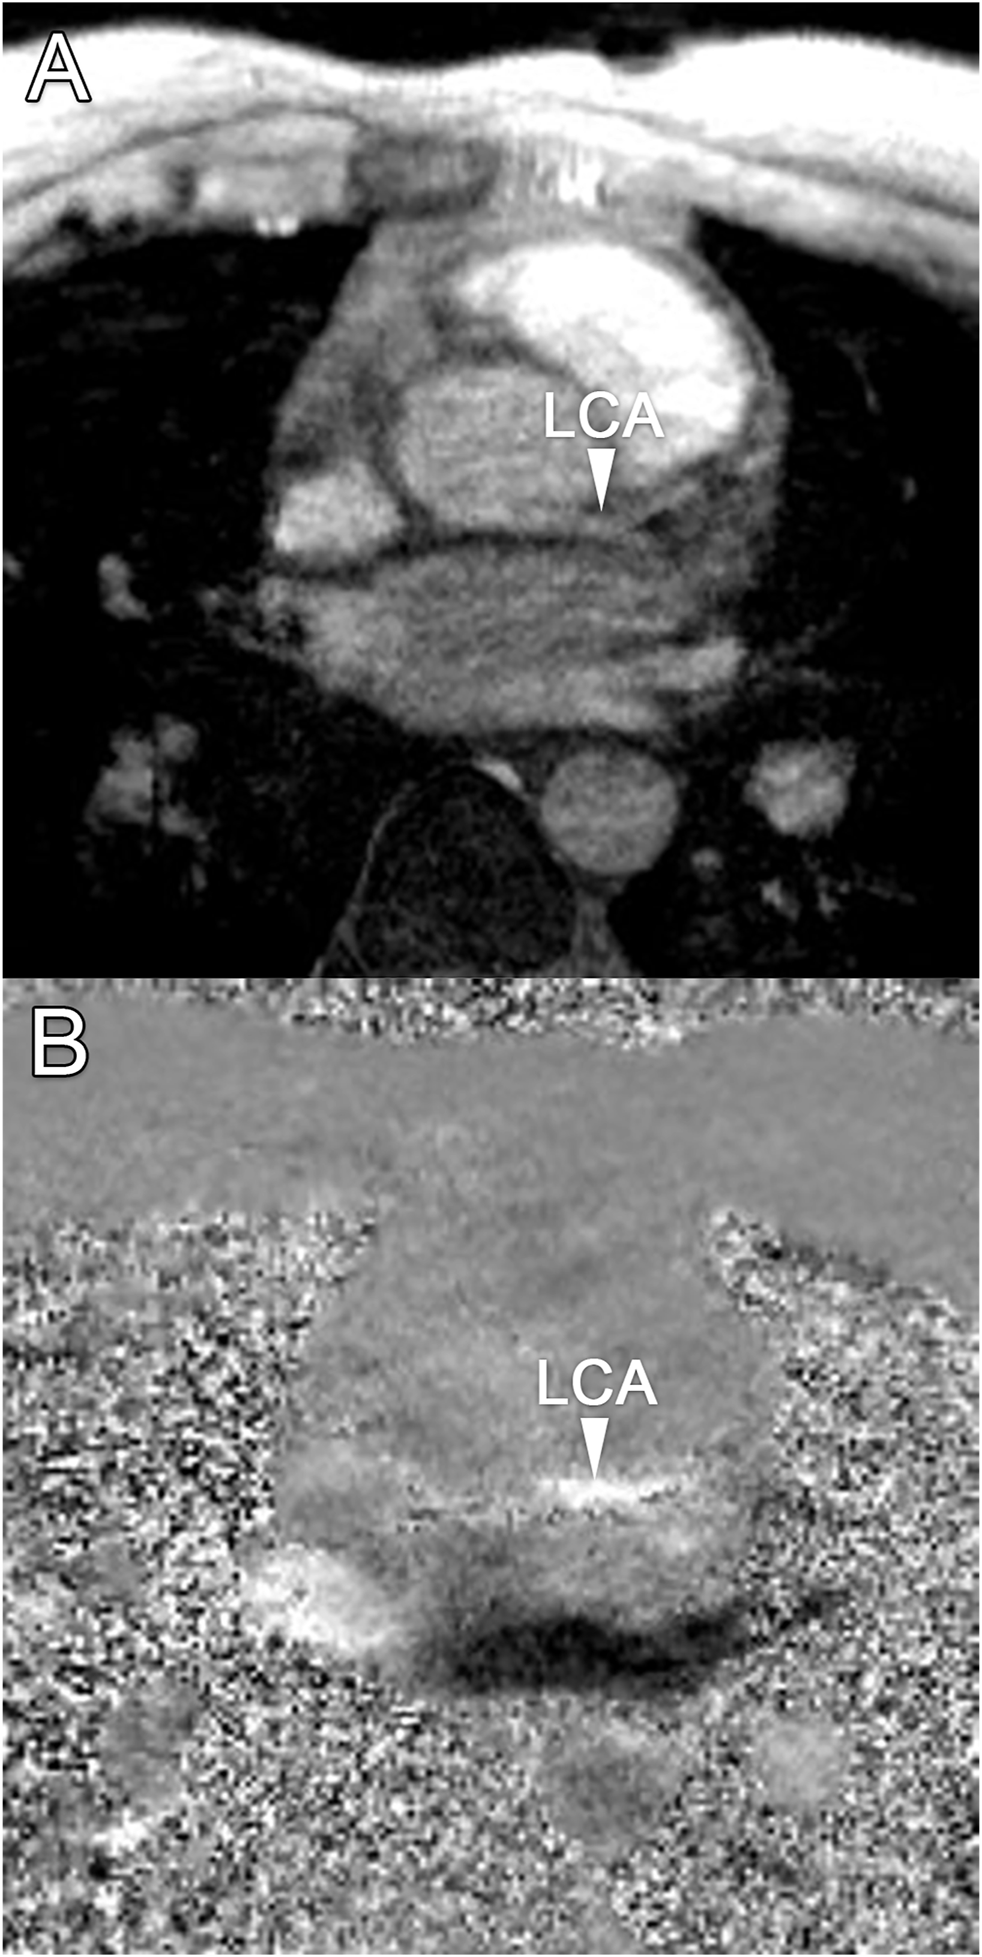

Median scan time was 12:20 min per 4D flow MRI scan (IQR: 11:30–13:15 min) with a respiratory gating efficiency of approximately 90%. Three subjects were excluded because of insufficient visibility of the LCA in both the original and motion-corrected reconstructions. In these subjects, a pattern of relatively long inspiration phases and no clear skewness towards end-expiration was observed. In the remaining eleven subjects (six female, five male, aged 28 ± 4 years), the LCA was identified in the magnitude images and velocity signal in the phase images. An overview of all original and corrected reconstructions can be found in Supplementary Figure S1. Figure 3 shows example images of phase-contrast magnitude and velocity in right-left direction. Figure 4 shows streamlines in the LCA, splitting into left anterior descending (LAD) and left circumflex (LCX) coronary artery. A video of the streamlines can be found in Supplementary Video S1. Flow curves from this acquisition are presented in Figure 5 (top). Seven out of 24 time frames were examined in this subject. In the other subjects, the number of examined cardiac frames ranged from 5 to 8.

FIGURE 3

www.frontiersin.org

FIGURE 3. (A) Transversal 4D flow MRI magnitude image and (B) phase image showing velocities in right-left direction during mid-diastole. Arrows indicate the location of the left coronary artery, where velocity signal can be observed.